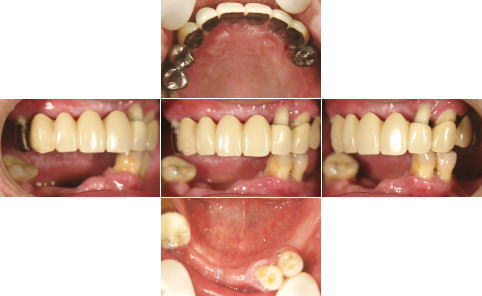

| 治療前 | 治療後 |

| 下顎の前歯部以外の全ての歯にグラツキがあったため、上顎はAll-on-4、下顎の奥歯は通常のインプラントブリッジとしました。 | |